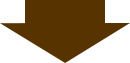

歯科用CTで親知らずの生え方を精密に把握し、難症例にも対応いたします。

親知らずは10代後半~30代にかけて生えてくる永久歯ですが、炎症や痛みを伴う「智歯歯周炎」を引き起こすことがあります。問題がなければそのまま永久歯として使うことができますが、精密検査を行った上でトラブルの可能性がある場合は抜歯を検討します。親知らずが生え始めたなと思ったら、痛みが出る前に歯科医院を受診しましょう。

歯科用CTによる画像診断を行って安全な抜歯を目指します

院内の歯科用CTで親知らずの位置や形状、血管や神経などを三次元的に把握することが可能なため、難しい抜歯にも対応することができます。経験や勘に頼ることなく、安全で精確な抜歯を心がけています。